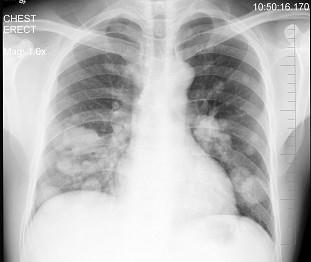

问题 男性,43岁,胸闷、胸痛10余天,不咳嗽不发热,X线检查如图,最合理的诊断是 ( )

选项 A.原发性肺癌 B.肺转移瘤 C.炎性假瘤 D.结核瘤 E.支气管扩张

答案 B